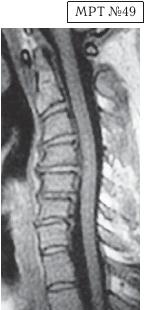

На МРТ № 49 наблюдается кифоз шейного отдела позвоночника, хотя он и не привёл к абсолютному стенозу спинномозгового канала позвоночника, однако значительно нарушил ликвородинамику. Вентральное эпидуральное пространство блокировано вершиной кифоза с экскавацией и оттеснением спинного мозга, а дорсальное эпидуральное пространство блокируется чуть ниже от вершины задней стенкой спинномозгового канала.